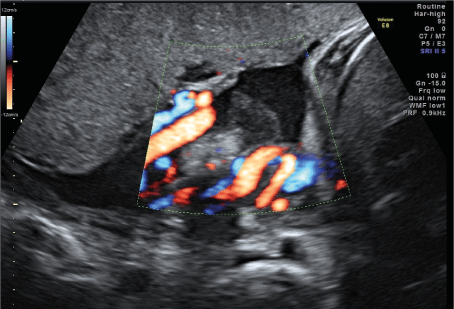

A 33-year-old woman in 32 weeks and 3 days of her third pregnancy was transferred to our unit for immediate delivery due to mayor concerns of her outpatient obstetrician regarding a rapidly developing cystic mass at the base of the placental umbilical cord with significant morphological changes within the last 14 days. The pregnancy had been uneventful up to this point. Sonography showed a timely developed fetus with a normal amount of amniotic fluid and normal Doppler parameters. There was a cystic structure of 42mm x 29mm x 41mm close to the placental insertion of the umbilical cord. Within the anechoic cystic mass, a spherical echo-rich structure of 23mm x 26mm x 28mm on a thin stalk without detectable vascularization was visible (Figures 1 and 2). The cyst was first noticed in the 3rd ultrasound scan at 30 weeks of gestation, but at that time it was still without internal structure. Due to the change in morphology the considered differential diagnosis were a thrombosed extra-abdominal umbilical vein varix as well as a placental or umbilical cord cyst.

Figure 2. Difficulty in differentiating whether the cyst originates primarily from the placenta or the umbilical cord